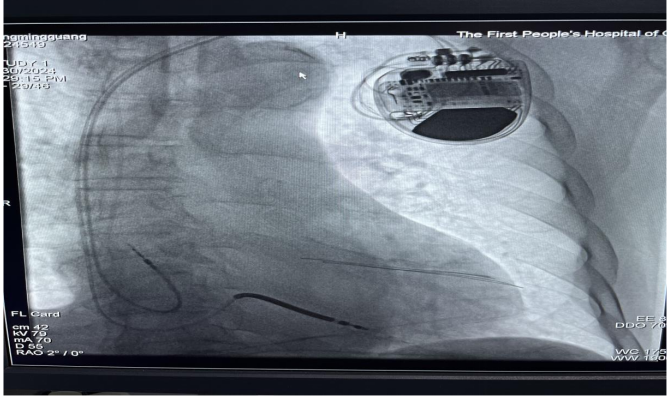

患者ICD植入后

7月30日,贵阳市第一人民医院心血管内科鲁玉明主任团队独立成功开展了一例植入式心律转复除颤器(ICD)植入术,成功为一位75岁的患者植入了一个叫做植入式心律转复除颤器(ICD)的小装置。这个小装置就像是一个随身携带的“守护神”,可以在心脏出现问题时,立即采取行动,保护心脏不受伤害。

经过充分评估讨论并与患者家属沟通后,鲁玉明主任团队决定为患者行植入式心律转复除颤器(ICD)植入术。手术在导管室局麻下顺利完成,由心内科黎姗姗副主任医师和许文主治医师共同操作。

术中出血少,患者各项参数良好,仅用时1小时20分钟便完成了手术,且患者术后恢复良好,患者及家属对治疗效果表示非常满意。